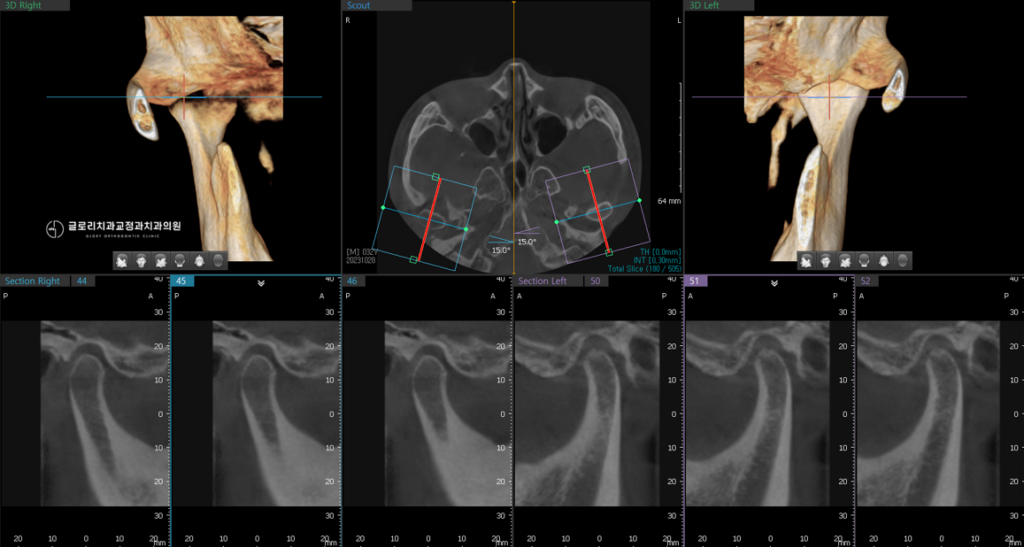

또한 턱관절에 무리가 가서 통증이 나타나거나 입을 벌릴 때 소리가 나는 증상이 생길 수 있기 때문에 사전에 턱관절 검사도 필수적으로 진행합니다.

이때 정밀 검사를 통해 발치 필요 여부를 신중하게 판단합니다.